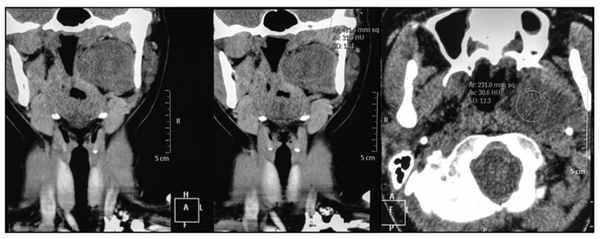

Из анамнеза: считает себя больной в течение 8 лет, с момента, когда заметила наличие образования в ротоглотке. Не лечилась и лишь год назад обратилась к ЛОР-врачу по месту жительства, который заподозрил аденому глоточного отростка. При магнитно-резонансной томографии обнаружено объемное образование глоточного отростка (рис. 1). Рис. 1. МРТ. Обратилась в ЦНИИС и ЧЛХ для проведения оперативного лечения.

При поступлении: состояние больной удовлетворительное. Данные эндоскопии: просвет носоглотки деформирован на 1/2 за счет компрессии извне по левой стенке. В полости рта: просвет глотки сужен вдающимся слева, подслизисто расположенным опухолевым образованием, занимающим боковую поверхность ротоглотки слева в проекции дужки и за ней (рис. 2, см. на цв. вклейке) Рис. 2. Вид мягкого неба с выбуханием опухоли глоточного отростка в просвет ротоглотки (а); просвет ротоглотки после операции (б). . Контуры лица и шеи деформированы из-за объемного опухолевого образования левой околоушной СЖ. Образование плотноэластической консистенции, безболезненное при пальпации. Регионарные лимфатические узлы не увеличены и не пальпируются.